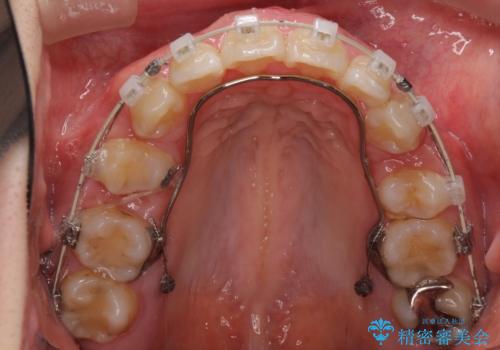

- 矯正装置

- 審美装置

- 治療期間

- 2年6ヶ月

- 治療回数

- 10-30回

上下左右の歯を1本ずつ、合計4本抜歯して、ワイヤー矯正を行うこととなりました。

右上の歯は、歯並び的には前から4番目の歯を抜歯したかったのですが、5番目の歯がすでに治療してある歯でしたのでこちらの歯を抜歯しました。

これにより少し治療期間が延びてしまいましたが、健康な歯を残すことができました。